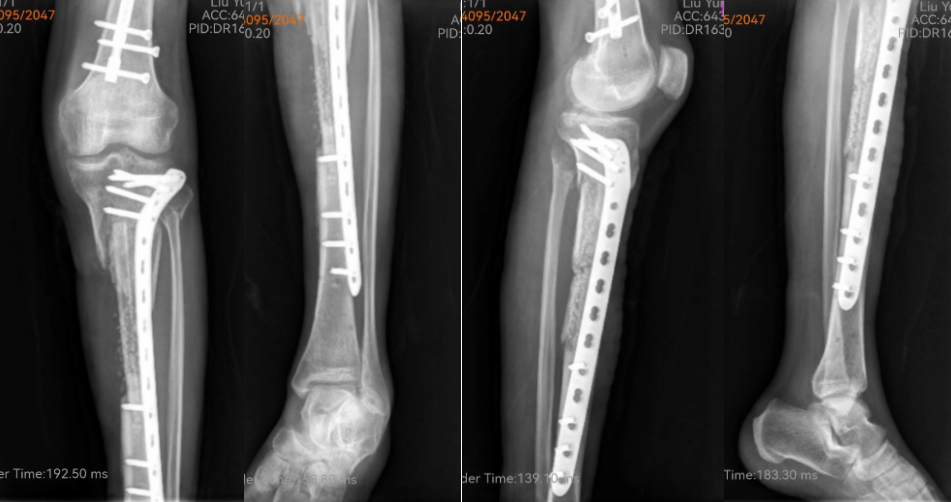

病例资料:患者男性,52岁,车祸致左股骨骨折、腰1椎骨折、左胫腓骨骨折,当地医院手术治疗,后出现感染,既往有慢性肾衰竭病史,持续血透治疗。6个月后我院就诊,给予反复清创、皮瓣转移、植皮、骨水泥珠链植入。以下为8周后无明显感征像的自体腓骨植入+人工骨植入+钢板内固定手术。